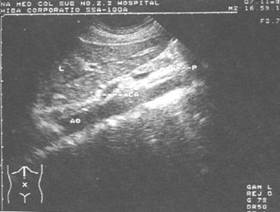

肝*腹主动脉纵切超声显像图——肝(L) 贲门(CA) 胰腺(P) 腹主动脉(AO)

所谓B超,其实是超声波B型显示成像的方法的简称。人体内部的肌体、器官的声速和密度都有差别,声波在由超声换能器发出,传入人体后在器官的界面和内部不均匀的地方就会有强弱不同的反射和散射回到人体表面的换能器上。通过对反射信号的处理,就可以显示出人身纵向切面各处的情况。